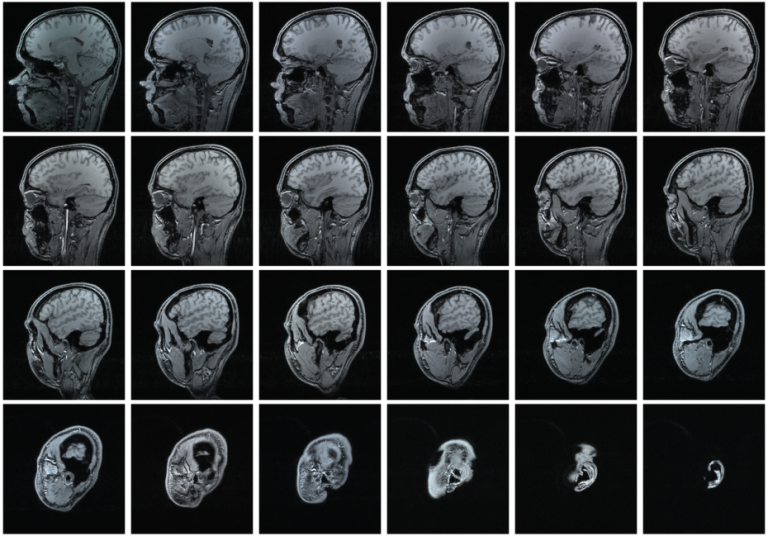

risonanza magnetica criteri di mc donald www istituto besta it

la risonanza magnetica encefalo nella diagnosi della sclerosi multipla medical imaging